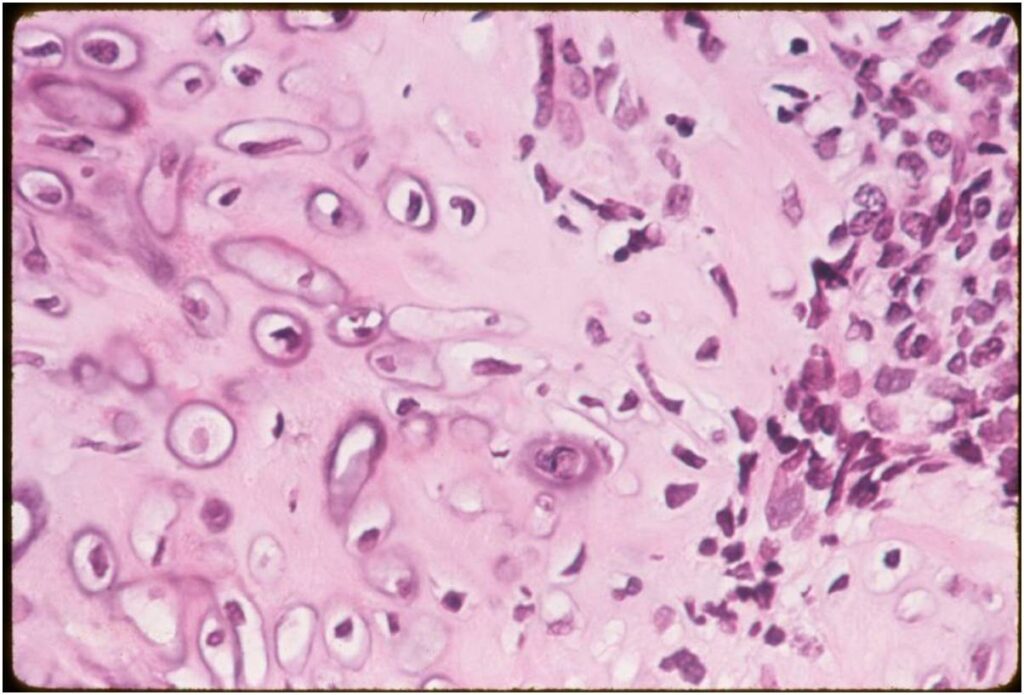

- Low grade islands of cartilage scattered throughout the mesenchymal cells

- Usually only a small part of lesion

- Cytologically low grade

- Usually sharply demarcated from surrounding stroma

- Stain S-100 positive

- Cells within cartilage

- Tend to have round or ovoid nuclei

- Lacunae are poorly formed

- May contain islands of collagen resembling osteoid

(Right Arrow) Cartilaginous Component